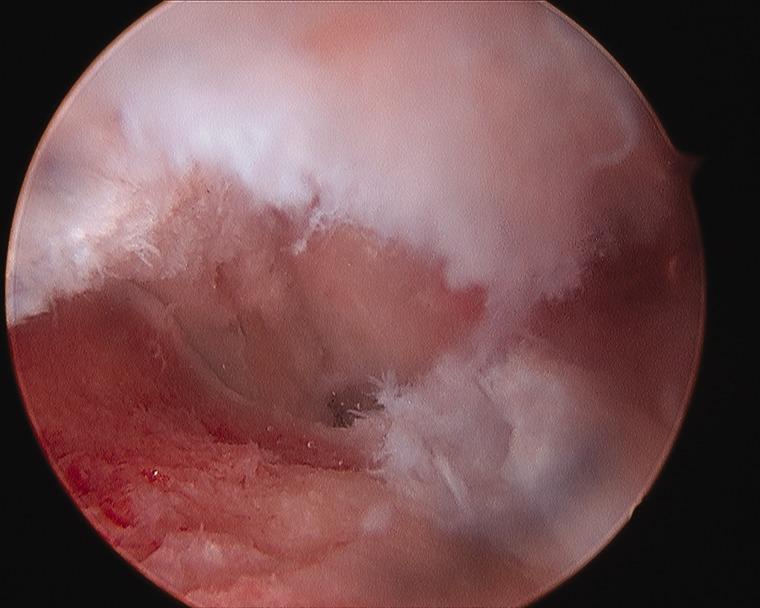

Arthroscopy of the pediatric hip began in 1977 with a publication by Gross. Interest was relatively slow to develop in the 1980s and 1990s. Coupled with the success of hip arthroscopy in the adult, interest heightened in applying the procedure to a variety of pediatric hip disorders, given that the alternative was an open surgical hip dislocation. The success of this initial group of pediatric hip arthroscopist's has further expanded the application of hip arthroscopy as the primary or adjunct procedure for the management of intra-articular problems of the pediatric hip.

小儿髋关节镜检查始于1977年格罗斯发表的一篇文章。在20世纪80年代和90年代,其发展相对缓慢。鉴于成人髋关节镜手术的成功,加上替代方案是开放性髋关节脱位手术,人们对将该手术应用于各种小儿髋关节疾病的兴趣日益浓厚。首批小儿髋关节镜医生取得的成功进一步扩大了髋关节镜检查作为治疗小儿髋关节关节内问题的主要或辅助手术的应用范围。